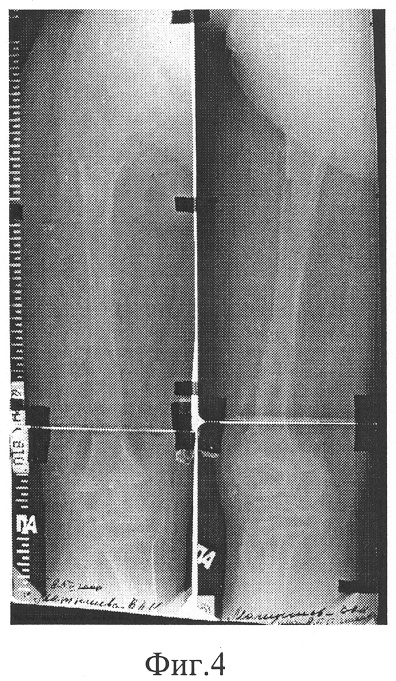

В послеоперационном периоде, начиная с 5-7 дня, производили дозированное продольное перемещение выделенных фрагментов обеих бедер. После появления рентгенологических признаков формирования костного регенерата в зонах дистракции – на 10 день – промежуточные фрагменты дозированно, в течение 5-ти дней, угловым разворотом средних опор отклонили от продольной оси сегментов на 15 градусов (фиг.2). При этом положение проксимального и дистального фрагментов оставили неизменным. Сохраняя приданное положение промежуточных фрагментов, продолжали продольную дистракцию до восстановления длины сегментов. Темп перемещения варьировали в пределах 0,5-1,0 мм в сутки на каждом из уровней дистракции, общая продолжительность которой составила 57 дней. Срок последующей фиксации в аппарате – 39 дней (фиг.3, 4). После демонтажа аппарата дополнительной иммобилизации конечности не производилось; больная прошла курс ЛФК.

В результате лечения длина бедер увеличена на 10 см. При этом в течение всего периода дистракции отмечалось равномерное формирование костных регенератов по всей площади противостоящих концов фрагментов с увеличением поперечных размеров (объема) регенератов после отклонения промежуточных фрагментов бедер от продольной оси сегментов. Это обеспечило оптимальные условия для последующей органотипической перестройки регенератов, что подтверждается минимальными для данной величины удлинения сроками аппаратной фиксации.